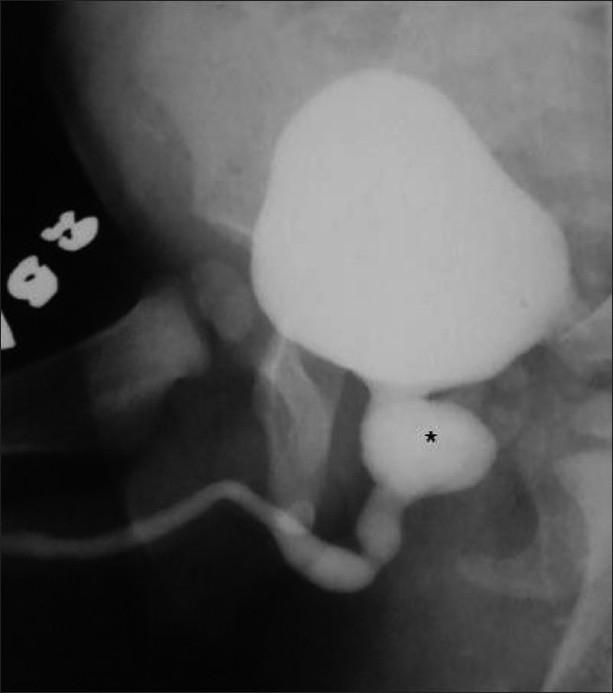

Congenital anomalies of the male urogenital tract are common. Some lesions like posterior urethral valve or anterior urethral diverticulum tend to present early in infancy and are often easily diagnosed on conventional contrast voiding cystourethrograms. Other conditions like posterior urethral diverticulum or utricle can be relatively asymptomatic and therefore present late in childhood. We present the spectrum of imaging findings of common and uncommon anomalies involving the male urethra. Since the pediatric radiologist is often the first to make the diagnosis, he or she should be well aware of these conditions.

男性泌尿生殖道先天性异常很常见。一些病变,如后尿道瓣膜或前尿道憩室,往往在婴儿期早期出现,通常在传统的排尿性膀胱尿道造影上很容易诊断。其他情况,如后尿道憩室或前列腺囊,可能相对无症状,因此在儿童期晚期出现。我们展示了涉及男性尿道的常见和罕见异常的影像学表现谱。由于儿科放射科医生往往是第一个做出诊断的人,他或她应该充分了解这些情况。